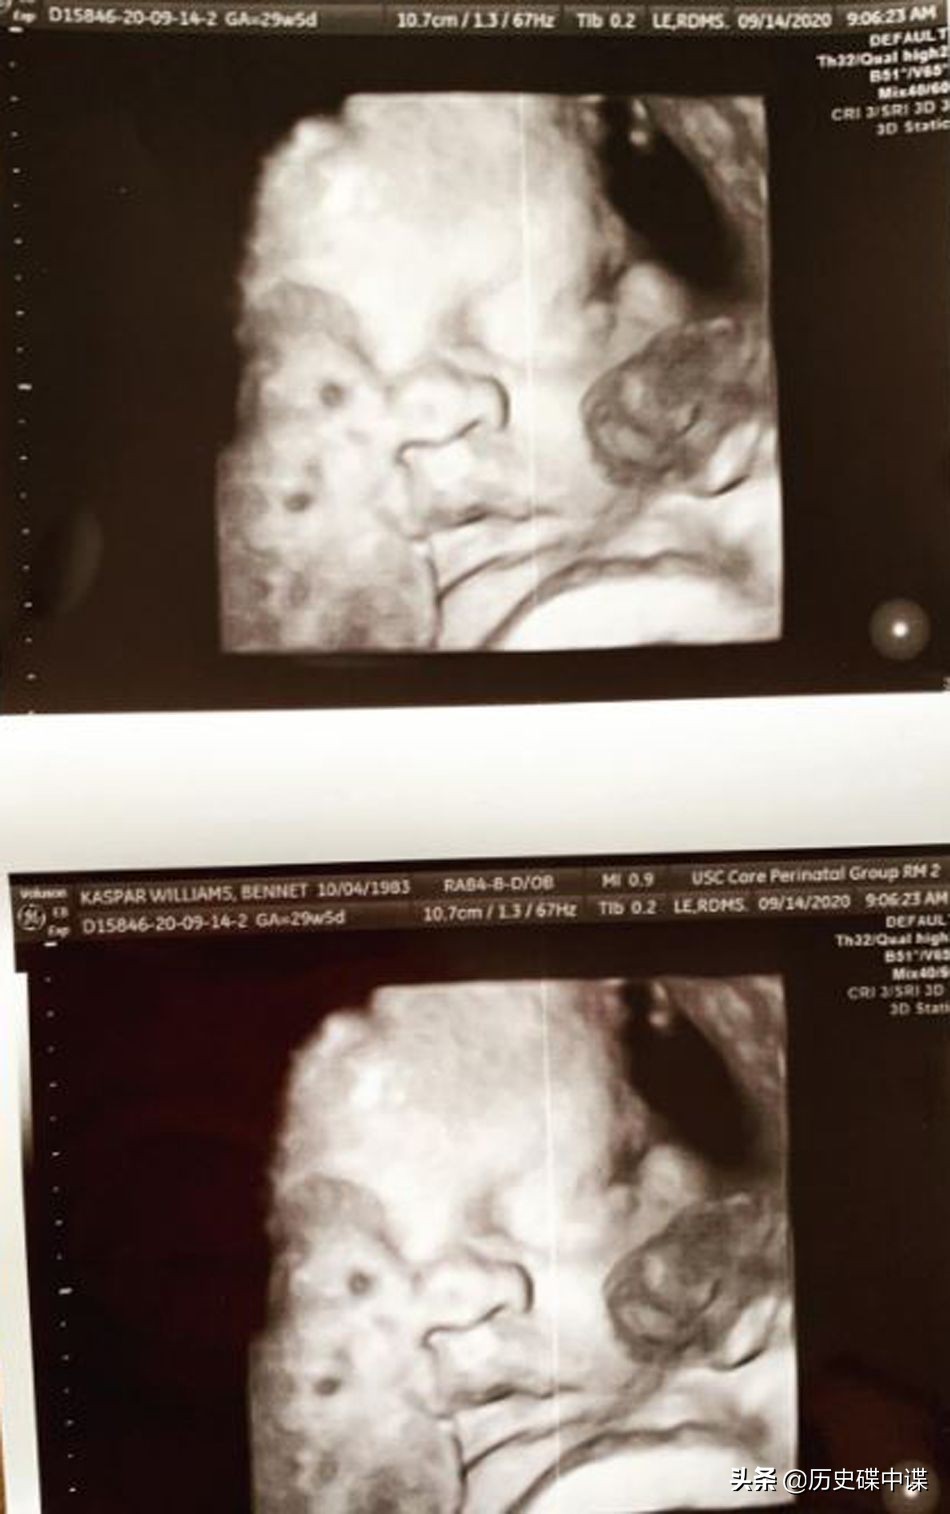

怀孕期间贝尔特的产检图像,宝宝十分健康